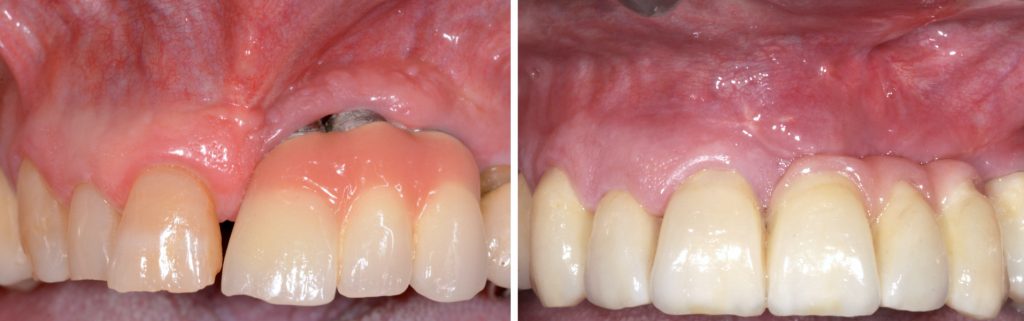

A la exploración clínica presenta implantes en posición de 21, 22 y 23 con una prótesis ceramo-metálica cementada con encía rosa donde se pueden apreciar las superficies de los implantes expuestas al medio oral (Figura 1).

Trascurrido el periodo de cicatrización, se realizaron las pruebas protésicas pertinentes y se colocó la prótesis definitiva (Figura 16).

Después de 12 meses de seguimiento se puede constatar el mantenimiento del resultado obtenido de forma satisfactoria tanto a nivel clínico, sin complicaciones biológicas ni mecánicas, como por parte del paciente (Figura 17).